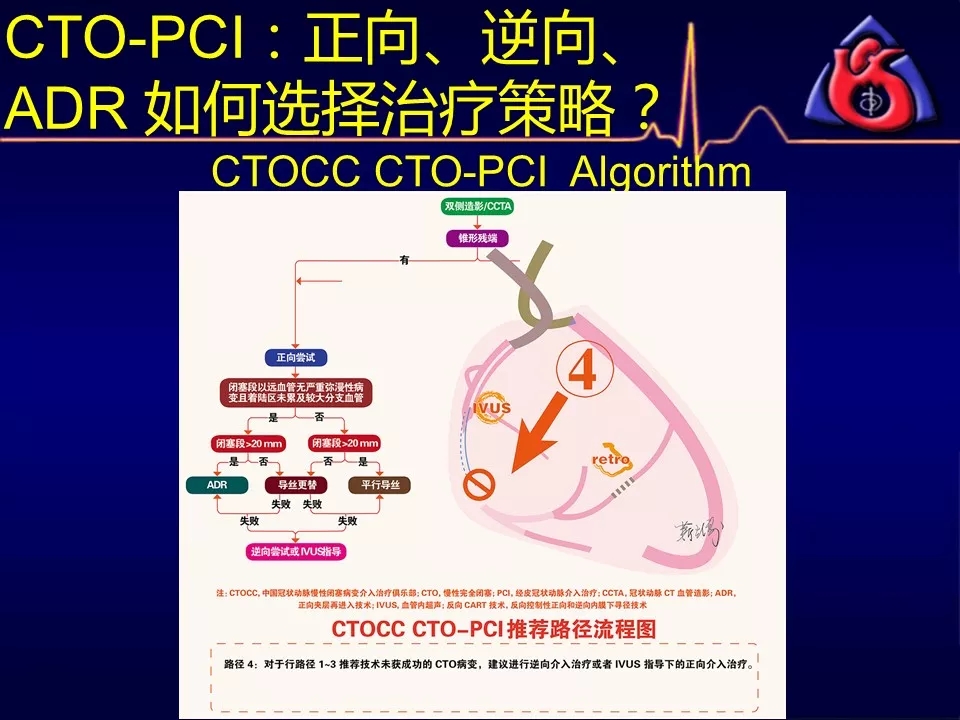

学习CTOCC CTO-PCI流程图的你

如何选择正向、逆向、IVUS指引及ADR技术?

《CTOCC CTO-PCI流程图精讲》

既往逆向技术尝试失败,再次逆向成功率不高者

当逆向技术困难时,如解剖条件许可,应优选ADR

逆向技术无条件(无可利用侧枝血管)